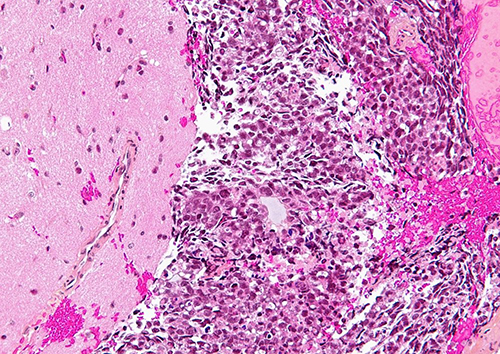

Ученые определили специальный белок, который, по-видимому, помогает предотвратить попадание опухолевых клеток в кровоток и распространение их в другие части тела.

Ученые обнаружили, что метастатические опухолевые клетки заметно снизили уровень этого сенсорного белка. Это позволило им эффективно войти в кровоток.

Результаты, опубликованные в журнале Science Advances, проливают свет на интравазацию – процесс, при котором раковые клетки, отделившиеся от первичной опухоли, попадают в кровоток, перемещаются в другие части тела, поражая их.

Ученые также показали, что искусственное увеличение экспрессии TRPM7 в опухолевых клетках может помочь остановить это процесс, а значит, предотвратить метастазирование.